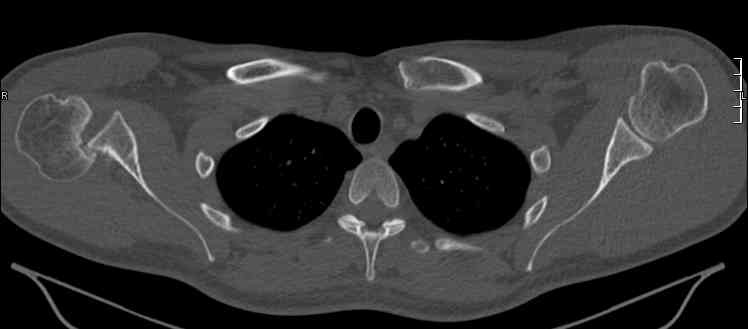

Задний вывих плеча действительно есть. Такой вариант вывиха по прямой рентгенограмме действительно не бросается в глаза. Травматологи-ортопеды в Молдавии есть.

Добрый день! А перелом Хилла-Сакса? Вывих-то можно вправить по Илизарову, а вот вывих+перелом? Какова перспектива?